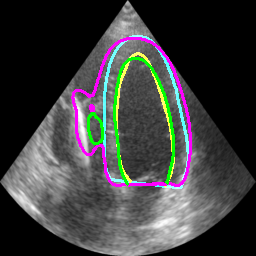

Table II displays the segmentation accuracy computed on the full dataset from patients having good and medium image quality ( patients) for the 4 algorithms described in section Sec. IV-D. Mean and standard deviation values for each metric were obtained from cross-validation on the 10 folds of the dataset. The values in bold correspond to the best scores for each metric. From these results, one can see that all the attention-based networks produced either the same, or better results than the baseline U-Net1, with AG-U-Net and LU-Net being the best performing models. Indeed, AG-U-Net obtained the overall best results for the segmentation of the LVEndo border ( value of mm and value of mm), leading to segmentation scores close but still higher than the intra-observer variability for this structure. The LU-Net-m5 approach obtained the best results for the segmentation of the LVEpi border ( value of mm and value of mm) and the lowest number of geometric outliers (%). Interestingly, these scores are either equivalent or lower than the intra-observer variability for this structure. It is also worth noting the robustness of the LU-Net model with respect to the choice of margin parameter, as margins of % and produce almost the same segmentation scores for all metrics. An illustration of the segmentation performance of the LU-Net-m5 network compared to the baseline U-Net1 model on three different cases is provided in Fig. 2.